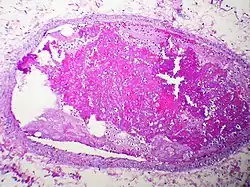

Embolism by other materials is rare. Septic embolism happens when a purulent tissue (pus-containing tissue) is dislodged from its original focus. Tissue embolism is analogous to macro-scale cancer metastasis, which happens when cancer tissue infiltrates blood vessels, and small fragments of tumor are released into the blood stream. Foreign-body embolism happens when exogenous—and only exogenous—materials such as talc enter the blood stream and cause occlusion or obstruction of blood circulation. Bullet embolism occurs in approximately 0.3% cases of gunshot wounds.[8] Amniotic-fluid embolism is a rare complication of childbirth.

Septic emboli may also be a contributor to spreading infection through the bloodstream to other tissues.[11]